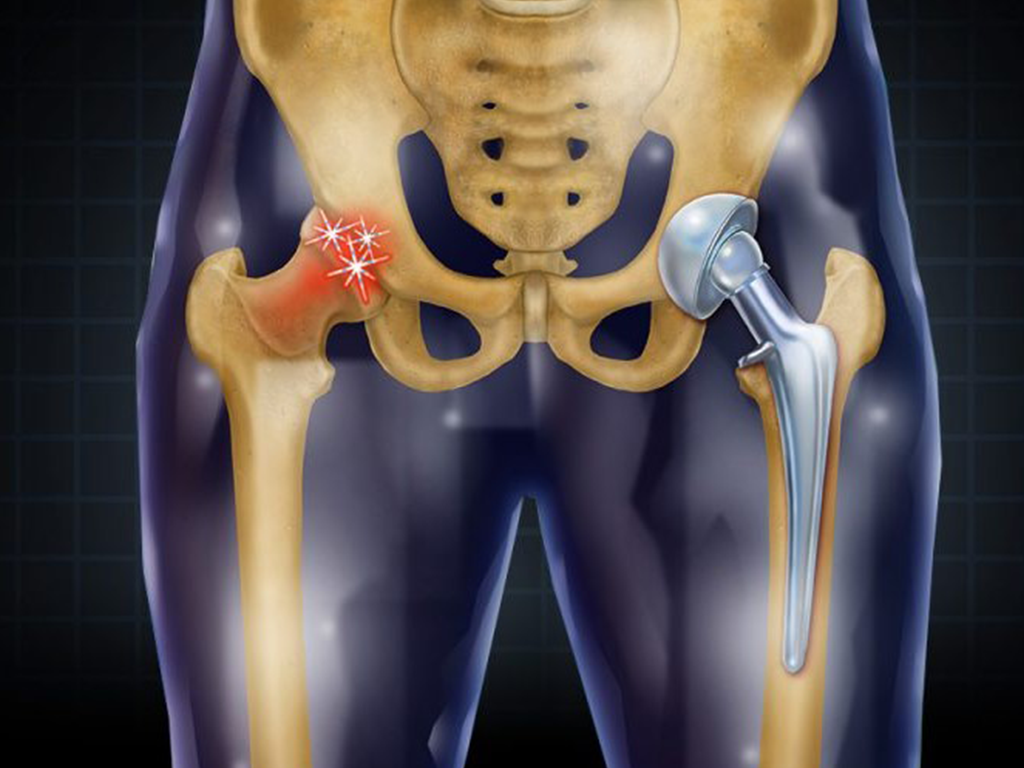

Hip replacement surgery Nagpur! Hip pain can significantly affect your daily life; however, with advanced medical care, relief is now possible. At Medicure Multispecialty Clinic in Nagpur, Dr. Romil Rathi offers advanced hip replacement surgery to help patients regain mobility, reduce pain, and return to an active lifestyle. Moreover, with modern surgical techniques and personalized care, patients receive world-class orthopedic treatment close to home.

Why Is Hip Replacement Surgery Need ?

Over time, the hip joint may deteriorate due to various conditions. Consequently, pain and stiffness increase, limiting daily activities. Therefore, hip replacement surgery becomes necessary when non-surgical treatments no longer provide relief.

Common Conditions That Require Hip Replacement

- Osteoarthritis – Gradual wear and tear of the hip joint

- Rheumatoid Arthritis – Chronic inflammation damaging joint surfaces

- Avascular Necrosis – Loss of blood supply to the hip bone

- Hip Fractures – Especially common in elderly patients

- Congenital Hip Disorders – Structural problems from birth

1. Total Hip Replacement (THR)

In this procedure, both the ball and socket of the hip joint are replaced. Consequently, it provides complete pain relief and improved movement.

2. Partial Hip Replacement

Here, only the damaged ball portion is replaced. Generally, this is suitable for certain fractures or specific conditions.